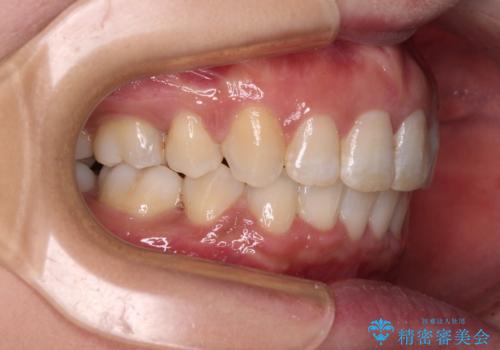

- 上の前歯の飛び出した感じと上下前歯のデコボコを気にして来院された患者様です。

叢生が強く、口元の突出感もあるため、上顎左右第一小臼歯4本を抜歯することとしました。

2年ほどインビザラインを使用しましたが、どうしても歯の移動がマウスピースに追随せず、全顎ワイヤー矯正へ切り替えました。

ワイヤー装着後は2年弱で、しっかりと仕上げることができました。